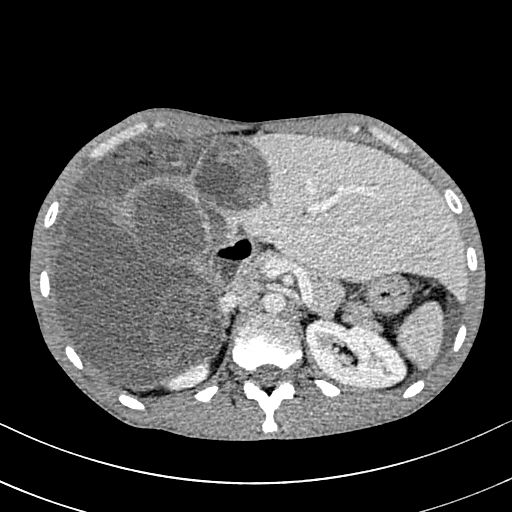

Histology is similar to hamartomas, although some state a lymphangiectasic or neoplastic nature, without any malignant potentiality [3]. Ultrasonography documents mono-or multiloculate fluid-superfluid lesions with a substantial lack of flow with Doppler mode (figure/patient 1-2). Computer Tomography (CT) describes low attenuation masses with occasional fluid level and minimum septal and peripheral enhancement. Magnetic resonance imaging (MRI) detects iso-or hyposignal on T1-weighted sequences and hyper-signal on T2-weighted sequences, a halo of enhancement around the septa of macro-cystic lesions and peri lesional lymphoedema (figure/patient 2-3) [4].

Sclerotherapy is nowadays largely employed in case of macro-cystic or mixed lymphangiomas, where the size of the cysts allows them to be punctured and a wider distribution of the agent is achieved. However, OK-432, bleomycin and above all doxycycline have recently proved effective also with micro-cystic variety [2]. The rationale comes from the observation that lymphangiomas can reduce their size or regress after a spontaneous infection, probably due to the destruction of the epithelium, reduction of lymph production and collapse of the cyst: thus, the idea of adopting sclerosing agents to mimic such an effect. Puncture of the dominant cyst (or more, in case they are noncommunicating) with a fine needle (20 G or more) is followed by aspiration (in order to enhance the SA effect) and injection, in one or more times, of the sclerosing agent, using the same amount as the aspirated fluid (if impossible, half of the lesion's volume). It can be repeated in case of partial response or whenever more administrations are chosen, each session being separated by weeks up to a month. General or loco-regional anaesthesia is preferred in children or uncooperative patients and in adults or small cystic malformations, respectively; the patient's position is changed many times to favour a uniform distribution of the agent and the treatment lasts up to two hours. A postoperative compressive bandage is advised in order to increment the time of contact between the solution and the cyst's wall and to prevent seroma formation, bleeding or effusion of the SA. The procedure can be performed under ultrasound or CT: the first is cheaper, more available, does not employ ionising radiations (thus being advisable in children and young adults), defines better the different components within the lesion, grants different cranio-caudal angles and reduces the risk of accidental puncture of large blood vessels; however, it is operator-dependent and offers a narrow field of view, with the risk of missing some important findings, especially at the post-procedure check. CT instead is easier to perform and provides a more panoramic view but implies radiation and the needle path to lie on the axial plane with its full length [1]; a detailed example of this procedure is offered in figure (patient) 4, whereas figures (patients) 5 and 6 show examples of successful outcomes comparing lymphangiomas before and after sclerotherapy. Fluoroscopic guidance is also reported, especially in case of the most superficial lesions, with the possibility to inject contrast medium into the lesion in order to highlight communications between the intra-lesional spaces and establish the amount of SA to be used [4]. Complications include intraoperative bleeding (due to their dysplastic nature), accidental injuries to nerves, vessels, organs and other tissues (due to extravasation), peri-lesional fibrosis and aesthetic sequelae (due to necrosis followed by second-intention reparation), dosedependent cardio-pulmonary toxicity (especially with bleomycin) and acute respiratory insufficiency (with large lymphangiomas undergoing inflammation, necrosis and quick volumetric expansion); the latter could be managed with dexamethasone or, preferably, avoided by splitting the treatment in more sessions [7]. An example of follow-up program would consist of a clinical examination after one to three weeks, ultrasonography after six to twelve weeks and then (depending on the results of ultrasound) MRI, unless evidence of early recurrence or any other complication occurs [8]. A review by Adams et al didn't prove the superiority of sclerotherapy over surgery but showed it was the treatment of choice in most major paediatric vascular anomaly centres: surgery was reserved for refractory cases, with sclerosing agents not improving either clinics or aesthetics, micro cystic lesions or those associated with life-threatening airway obstruction. Nowadays there are no worldwide-accepted guidelines and patient selection seems to guide the choice. In addition, neither surgery nor sclerotherapy can guarantee complete healing with just one session: it is actually advisable to perform multiple treatments or combine them [1].